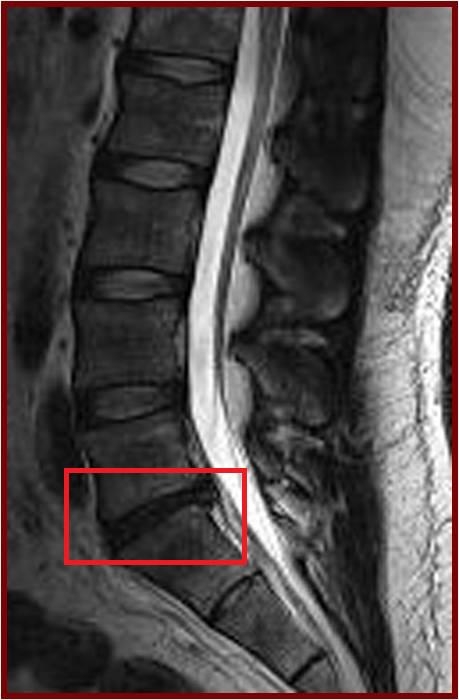

今次的研究是一項以南中國地區人口而作出的具代表性抽樣研究,從上述大型人口群組中抽出21歲或以上的成年人為研究對象。在是次的研究中,研究人員分析了合共2,599位成年人的磁力共振(MRI)檢查數據。當中27%(709人)沒有椎間盤退化,而73%(1,809人)則有椎間盤退化。在患有椎間盤退化的成年人當中,有7%體重過輕,48%體重正常,36%過重和9%肥胖。超重及肥胖的成年人出現椎間盤退化程度及發展成更嚴重的病徵的機會,比正常體重或過輕的成年人嚴重。